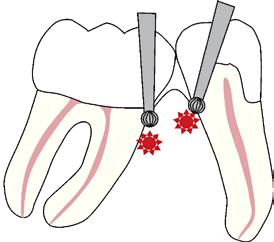

Fig. 1. A. Udsnit af panoramaoptagelse viser Ca(OH)2 uden for foramen apicale i en overkæbemolar og i sinus maxillaris (pil). B. Periapikal optagelse viser Ca(OH)2 uden for foramen apicale (pil) i en central incisiv. Tilfældet krævede kirurgisk indgreb.

Ved mistanke om malpraksis vurderer man behandlerens handlinger i alle stadier i relation til opgavens kompleksitet og tager stilling til, om disse lever op til normen for almindelig anerkendt faglig standard. De mest omfattende skadevirkninger ses i forbindelse med anvendelse af endodontiske skyllevæsker og andre medikamenter, fx ulykker med natriumhypoklorit eller skader på nervevæv eller i sinus som følge af udpresning af calciumhydroxid igennem foramen apicale (Fig. 1A og B) (5,6). Sådanne uheld vurderes ofte til at være undgåelige, idet tandlægen ikke har levet op til normal faglig standard. Frygt for at begå procedurefejl eller andre utilsigtede hændelser bør dog ikke få klinikeren til helt at afstå fra at foretage endodontiske behandlinger (7).